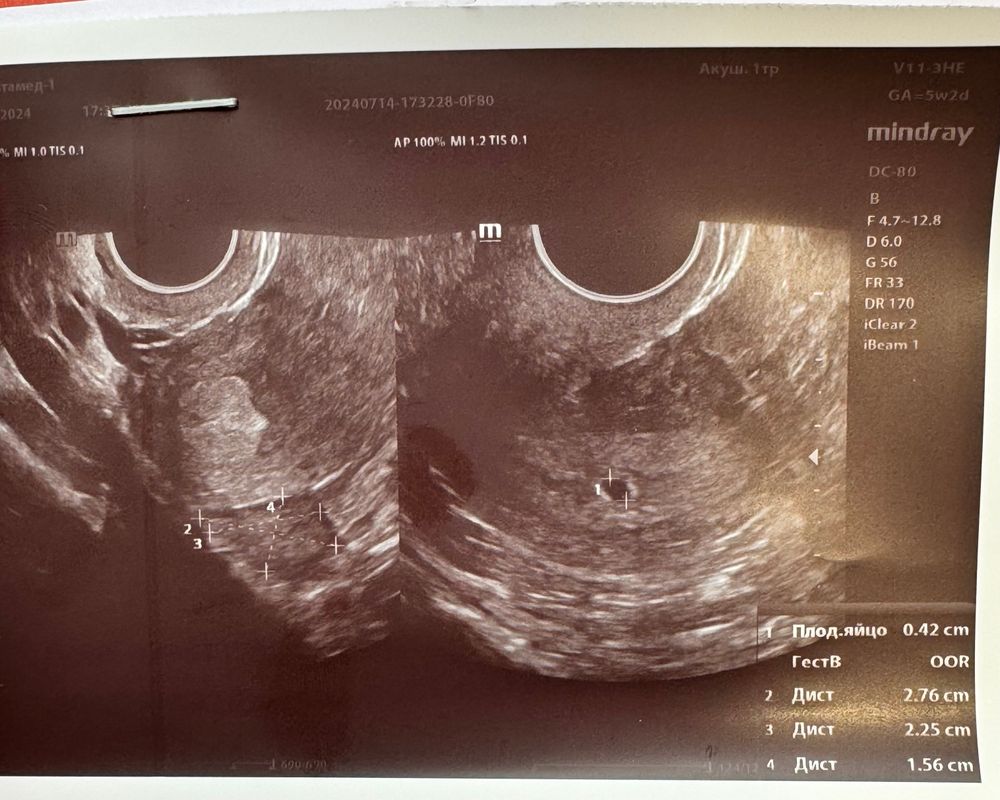

УЗИ акушерский срок 5 недель 2 дня

Да, это пя, все хорошо, придите на узи повторно через неделю )

Дарья, врач назначил еще сдать ХГЧ, через 48 часов и через 5 дней УЗИ

Да, все отлично! ПЯ по сроку, хгч растет как надо!